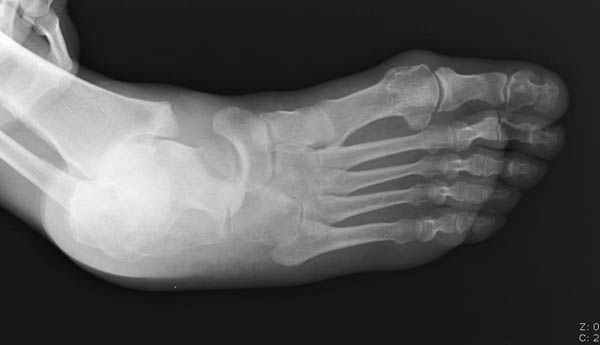

из

Уважаемые участники русского Ортофорума, поздравляю всех со всеми прошедшими праздниками: Новым годом, Рождеством, Hanukkah, Kwanzaa, желаю участникам всего наилучшего и здоровья. Повреждение таранной кости. Больной 81г автоавария, повреждение таранной кости, здесь снимки.

Какие рекомендации? Djoldas Kuldjanov, MD Department of Orthopedic Surgery St. Louis University Medical Center